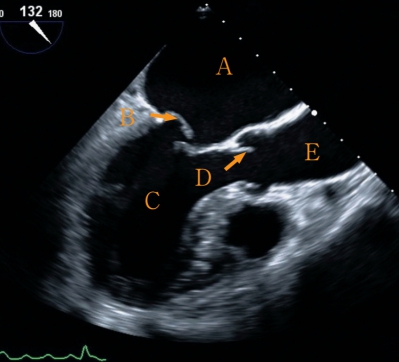

収縮期と拡張期の経食道心臓超音波像を別に示す。

正しいのはどれか。2つ選べ。

a. Aは右心房である。

b. Bは僧帽弁である。

c. Cは左心室である。

d. Dは肺動脈弁である。

e. Eは左心房である。